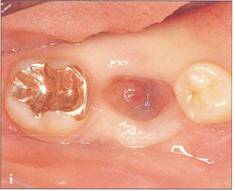

Fi 545e45f g 5-1f After extraction offirst molar from the recipient site. Fi 545e45f g 5-1 g The donor tooth. Note the adequate root form and amount of periodontal ligament on the root. Fi 545e45f g 5-1 h Measurement of the mesiodistal width of the donor tooth. |

Fi 545e45f g 5-1 i Measurement of the mesiodistal width of the recipient site. If the mesiodistal width of the donor tooth is greater than that of the recipient site, the proximal walls of the adjacent teeth are reduced to fit the donor tooth. Fi 545e45f g 5-1j Preparation of the recipient site. Removal of alveolar septum is done with a minirongeur. Fi 545e45f g 5-1 k After removal of the alveolar septum. |